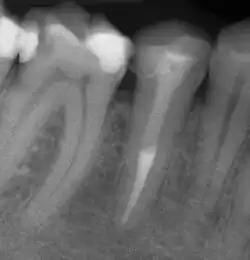

Zur Beurteilung des Erfolges einer Wurzelkanalbehandlung werden klinische Beschwerden, wie Schmerzen, Schwellungen oder Fistelgänge sowie der röntgenologische Befund herangezogen. Oft sind trotz endodontischer Infektion keine klinischen Beschwerden vorhanden, weshalb gerade die röntgenologische Kontrolle Hauptkriterium für die Beurteilung ist.[10] Neben der vorhandenen Wurzelfüllung und Veränderungen in der Wurzelphysiognomie (Resorptionen) wird vor allem der Zustand des periapikalen Gewebes begutachtet und auf das Vorhandensein einer Parodontitis apikalis oder einer radikulären Zyste geprüft.

- Wurzelkanalbehandelte Zähne mit röntgenologisch oder klinisch insuffizienter Wurzelkanalfüllung (z. B. mangelhafte Homogenität der Füllung, nicht behandelte Wurzelkanäle, nicht gefüllte Areale des endodontischen Systems, fragwürdiges und nicht mehr indiziertes Füllmaterial etc.) ohne klinische oder röntgenologische Anzeichen einer Parodontitis apicalis.

Wenn eine Verbesserung des Ausgangszustandes und eine Beseitigung der möglichen Ursachen nicht zu erwarten sind oder die Erhaltung des Zahns fragwürdig ist, ist von einer Revision abzusehen. Ebenso müssen nicht-endodontische Ursachen der Erkrankung vor einem Eingriff ausgeschlossen werden.[1] Nach Strindberg et al. wird der endodontische Misserfolg nach einer ausreichenden Heilungszeit von vier Jahren mit dem Vorhandensein einer residuellen, persistierenden oder progredienten röntgenologischen Aufhellung (Dunkler Punkt an der Wurzelspitze im Röntgenbild) und/oder mit dem Vorhandensein klinischer Beschwerden jeglicher Form definiert.[18]